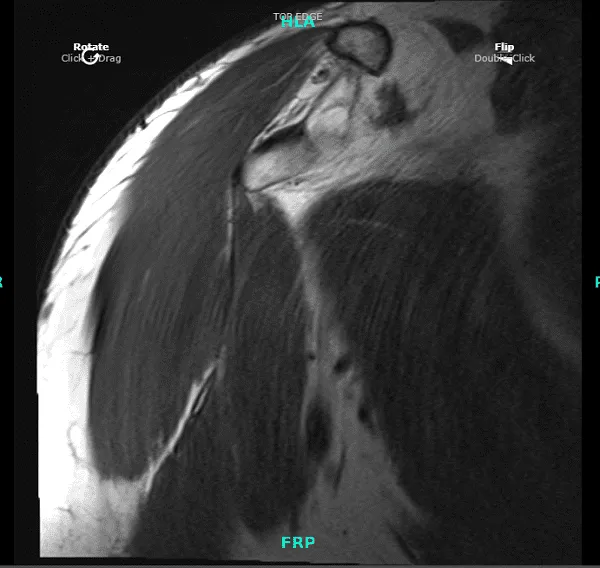

Tras una semana, el paciente presentó su resonancia magnética. Impresión de la siguiente manera: supraespinoso leve a moderado y tendinosis infraespinosa, con deshilachado bursal leve de las fibras de la zona de la unión de la zona. Pequeña rotura intersticial de bajo grado dentro del tendón subescapular inferior.

Antecedentes tendinosis subescapularis leve-moderada, con fisuras intrasustanciales de bajo grado superior. Rotura completa frente a casi completa del segmento intraarticular del tendón del bíceps, con retracción de los muñones distales del tendón del surco bicipital. Corto adicional y una división segmentada que desgarran el tendón extraarticular del bíceps.

El muñón corto del ancla del bíceps permanece unido al margen glenoideo superior. Desgarro del labrum posterosuperior (9-1:00, asociado a un quiste paralabral grande que sigue la vía medial y anterosuperior; el lóculo del quiste dominante se sitúa por delante del músculo supraespinoso. Artrosis acromioclavicular moderada. Bursitis subacromial leve. Espolóns subacromiales leves.